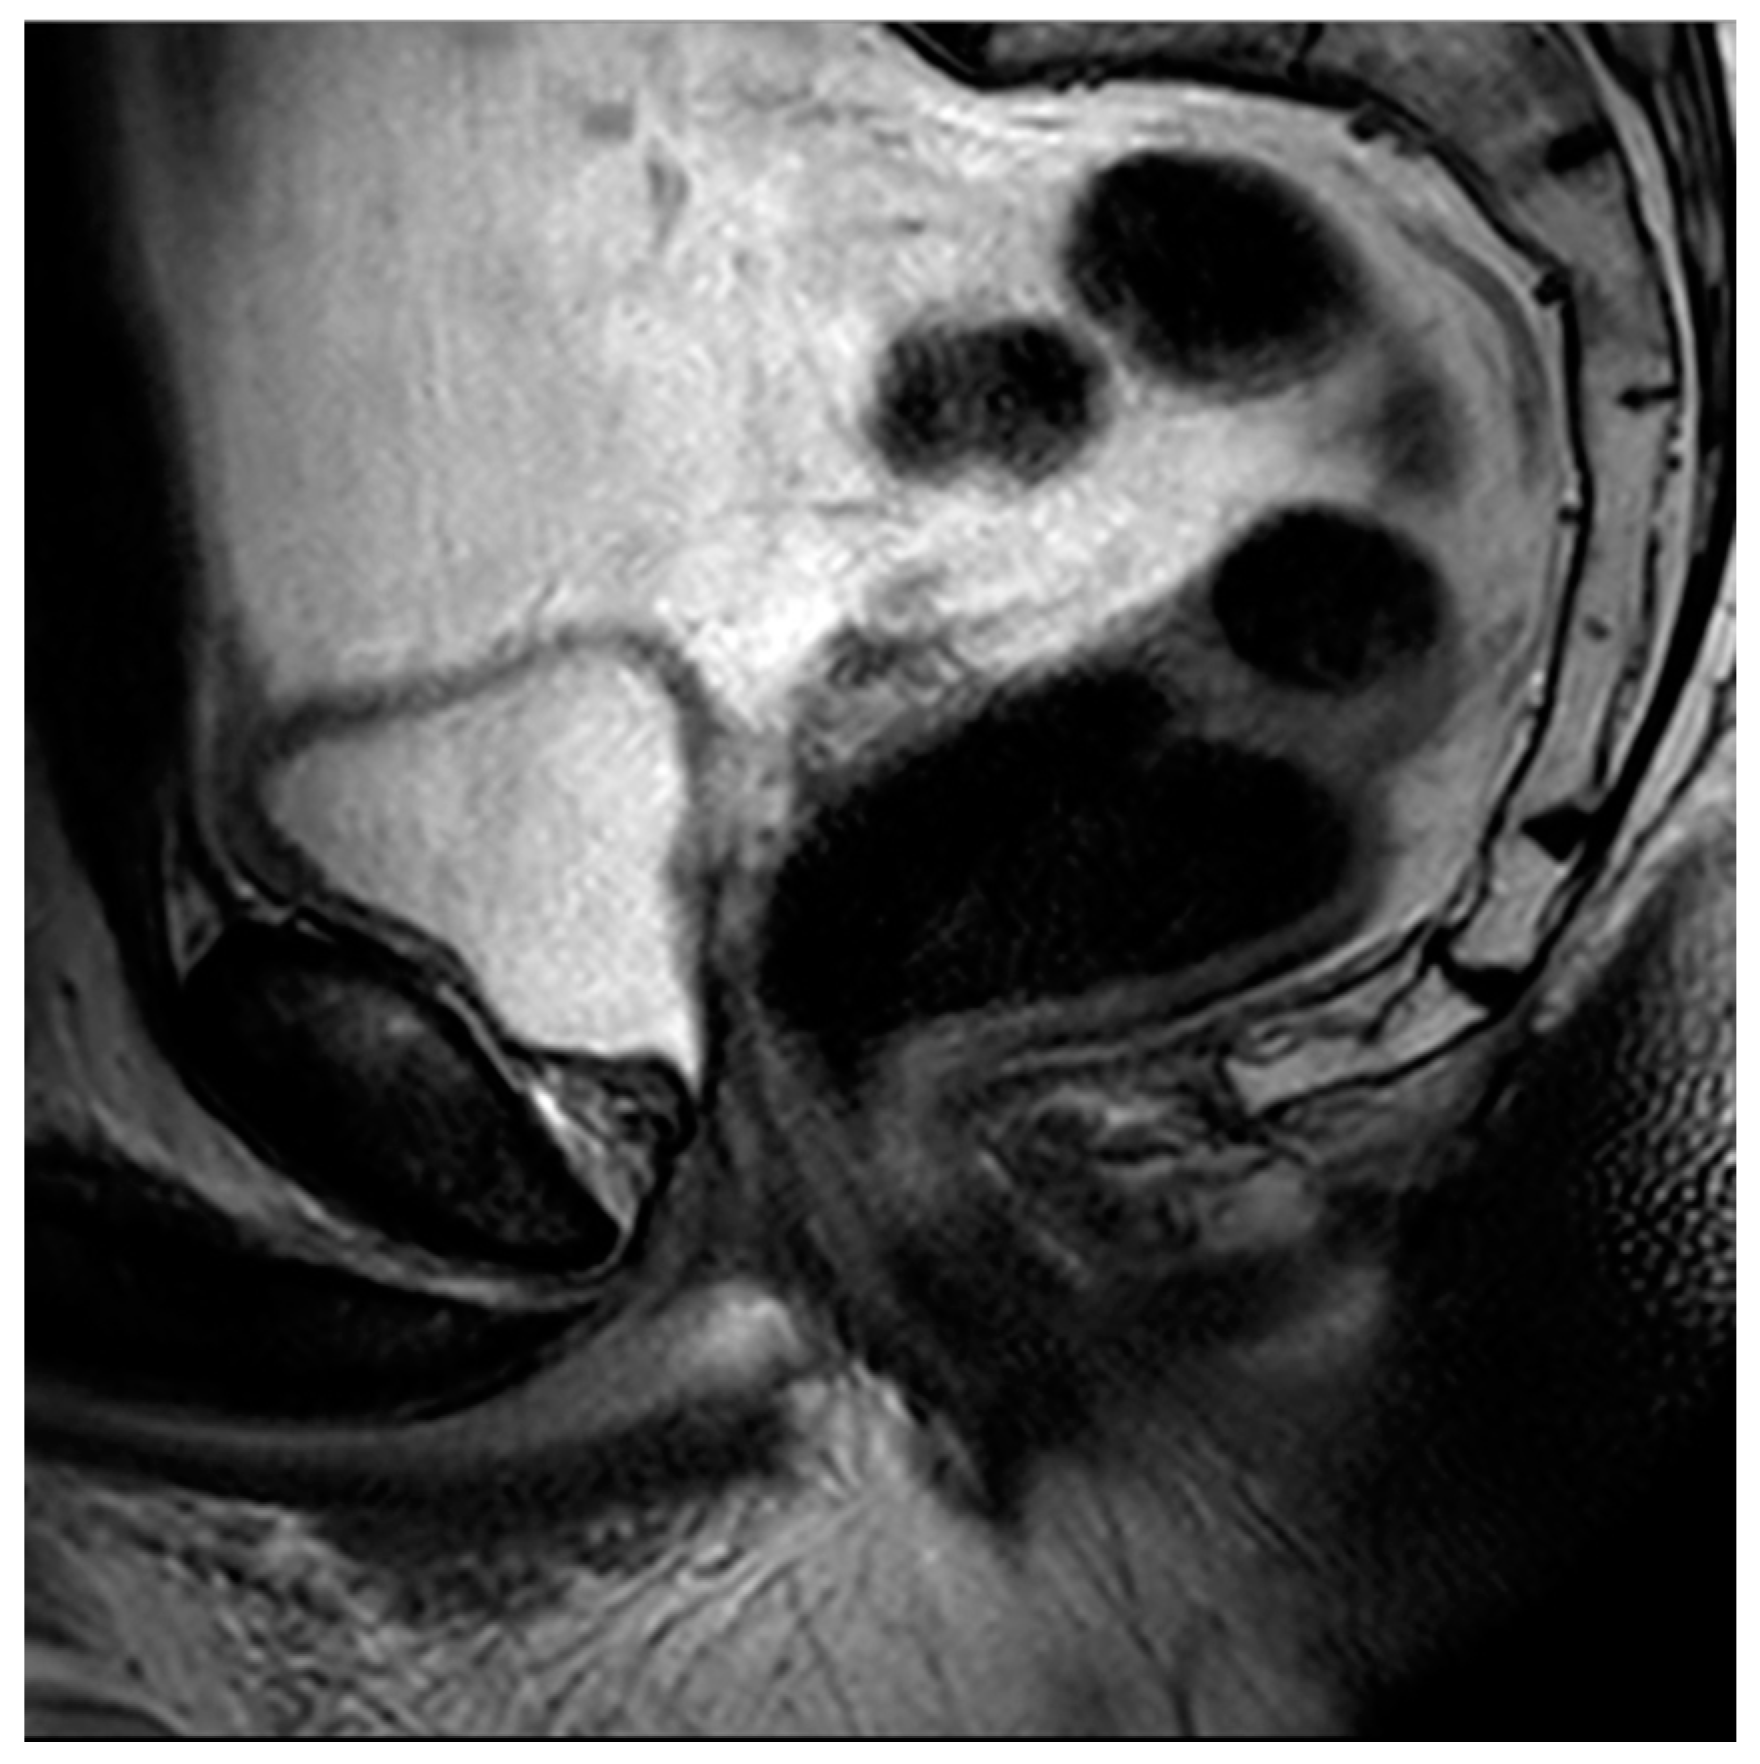

Figure 5. Sagittal T2 image demonstrating post-TURP changes of the prostate. Note the central defect at the level of the prostatic urethra and the relative absence of a median lobe.

Figure 6. Sagittal T2 image demonstrating post-HoLEP changes to the prostate. As compared to TURP, HoLEP features a wider central defect with less residual peripheral tissue.

The historical mainstay of surgical BPH is the transurethral resection of prostate tissue (TURP) [70]. This involves inserting a thin-loop wire electrode via a cystoscope and resecting adenomatous tissue in the prostatic transition zone that is responsible for bladder outlet obstruction (Figure 4). When using MRI, these changes typically present with an elongated, somewhat irregular appearance of the bladder neck and central prostate gland (Figure 5).

Laser enucleation of the prostate (LEP), commonly performed with either a holmium laser (HoLEP) or a thulium laser (ThuLEP), is an ever-increasingly used option for the treatment of BPH. These lasers were first used to vaporize tissue but are now more commonly used to enucleate the entirety of the gland, which is then mechanically morcellated within the bladder in order to facilitate expulsion. One major advantage of LEP, when compared to TURP, is that it is size-independent and can be implemented as a surgical option for glands of varying sizes [71]. When using MRI, LEP procedures look very similar to TURP but often have less residual peripheral tissue and a wider central periurethral defect (Figure 6). There can also be increased T2 intermediate signal and heterogeneity, which can impair the detection of prostate cancers.